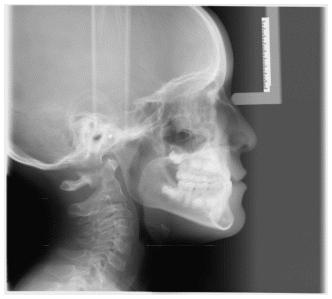

The patient was a young female presenting with a Class III dento-skeletal malocclusion, which was treated using the AMCOP® TC appliance. A comprehensive diagnostic protocol was carried out both before and after treatment, including orthopantomography (Figure 2–3), postero-anterior teleradiography (Figures 4, 5), latero-lateral cephalometric radiography (Figures 6, 7), cephalometric analysis (Tables 1, 2), as well as extraoral (Figures 8, 9) and intraoral photographs (Figures 10, 11). The extraoral examination revealed an edge-to-edge incisal relationship and the presence of a midline diastema. Pre-treatment cephalometric analysis (Deltadent® Lana, Bolzano, Italy) confirmed the diagnosis of a skeletal Class III malocclusion. The treatment plan involved the use of the AMCOP® TC appliance. The patient was instructed to wear the device for two hours in the afternoon and throughout the night for the first six months, followed by nighttime use only for an additional six months. Upon completion of the treatment, the patient achieved a Class I occlusion, with correction of both overjet and overbite. Additionally, the device facilitated tongue re-education and contributed to the postural realignment of the first cervical vertebra.